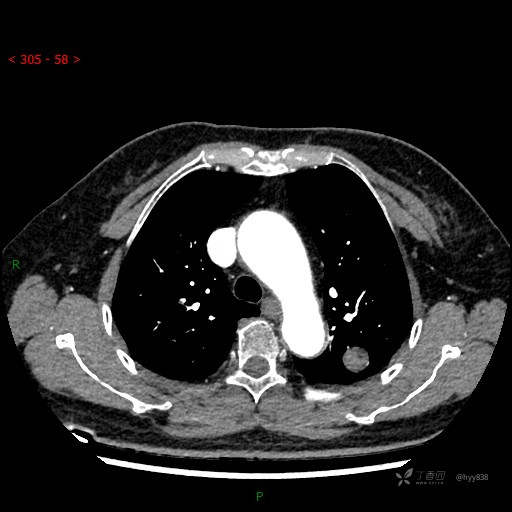

胸部CT平扫

各期CT值:28hu、58hu、69hu